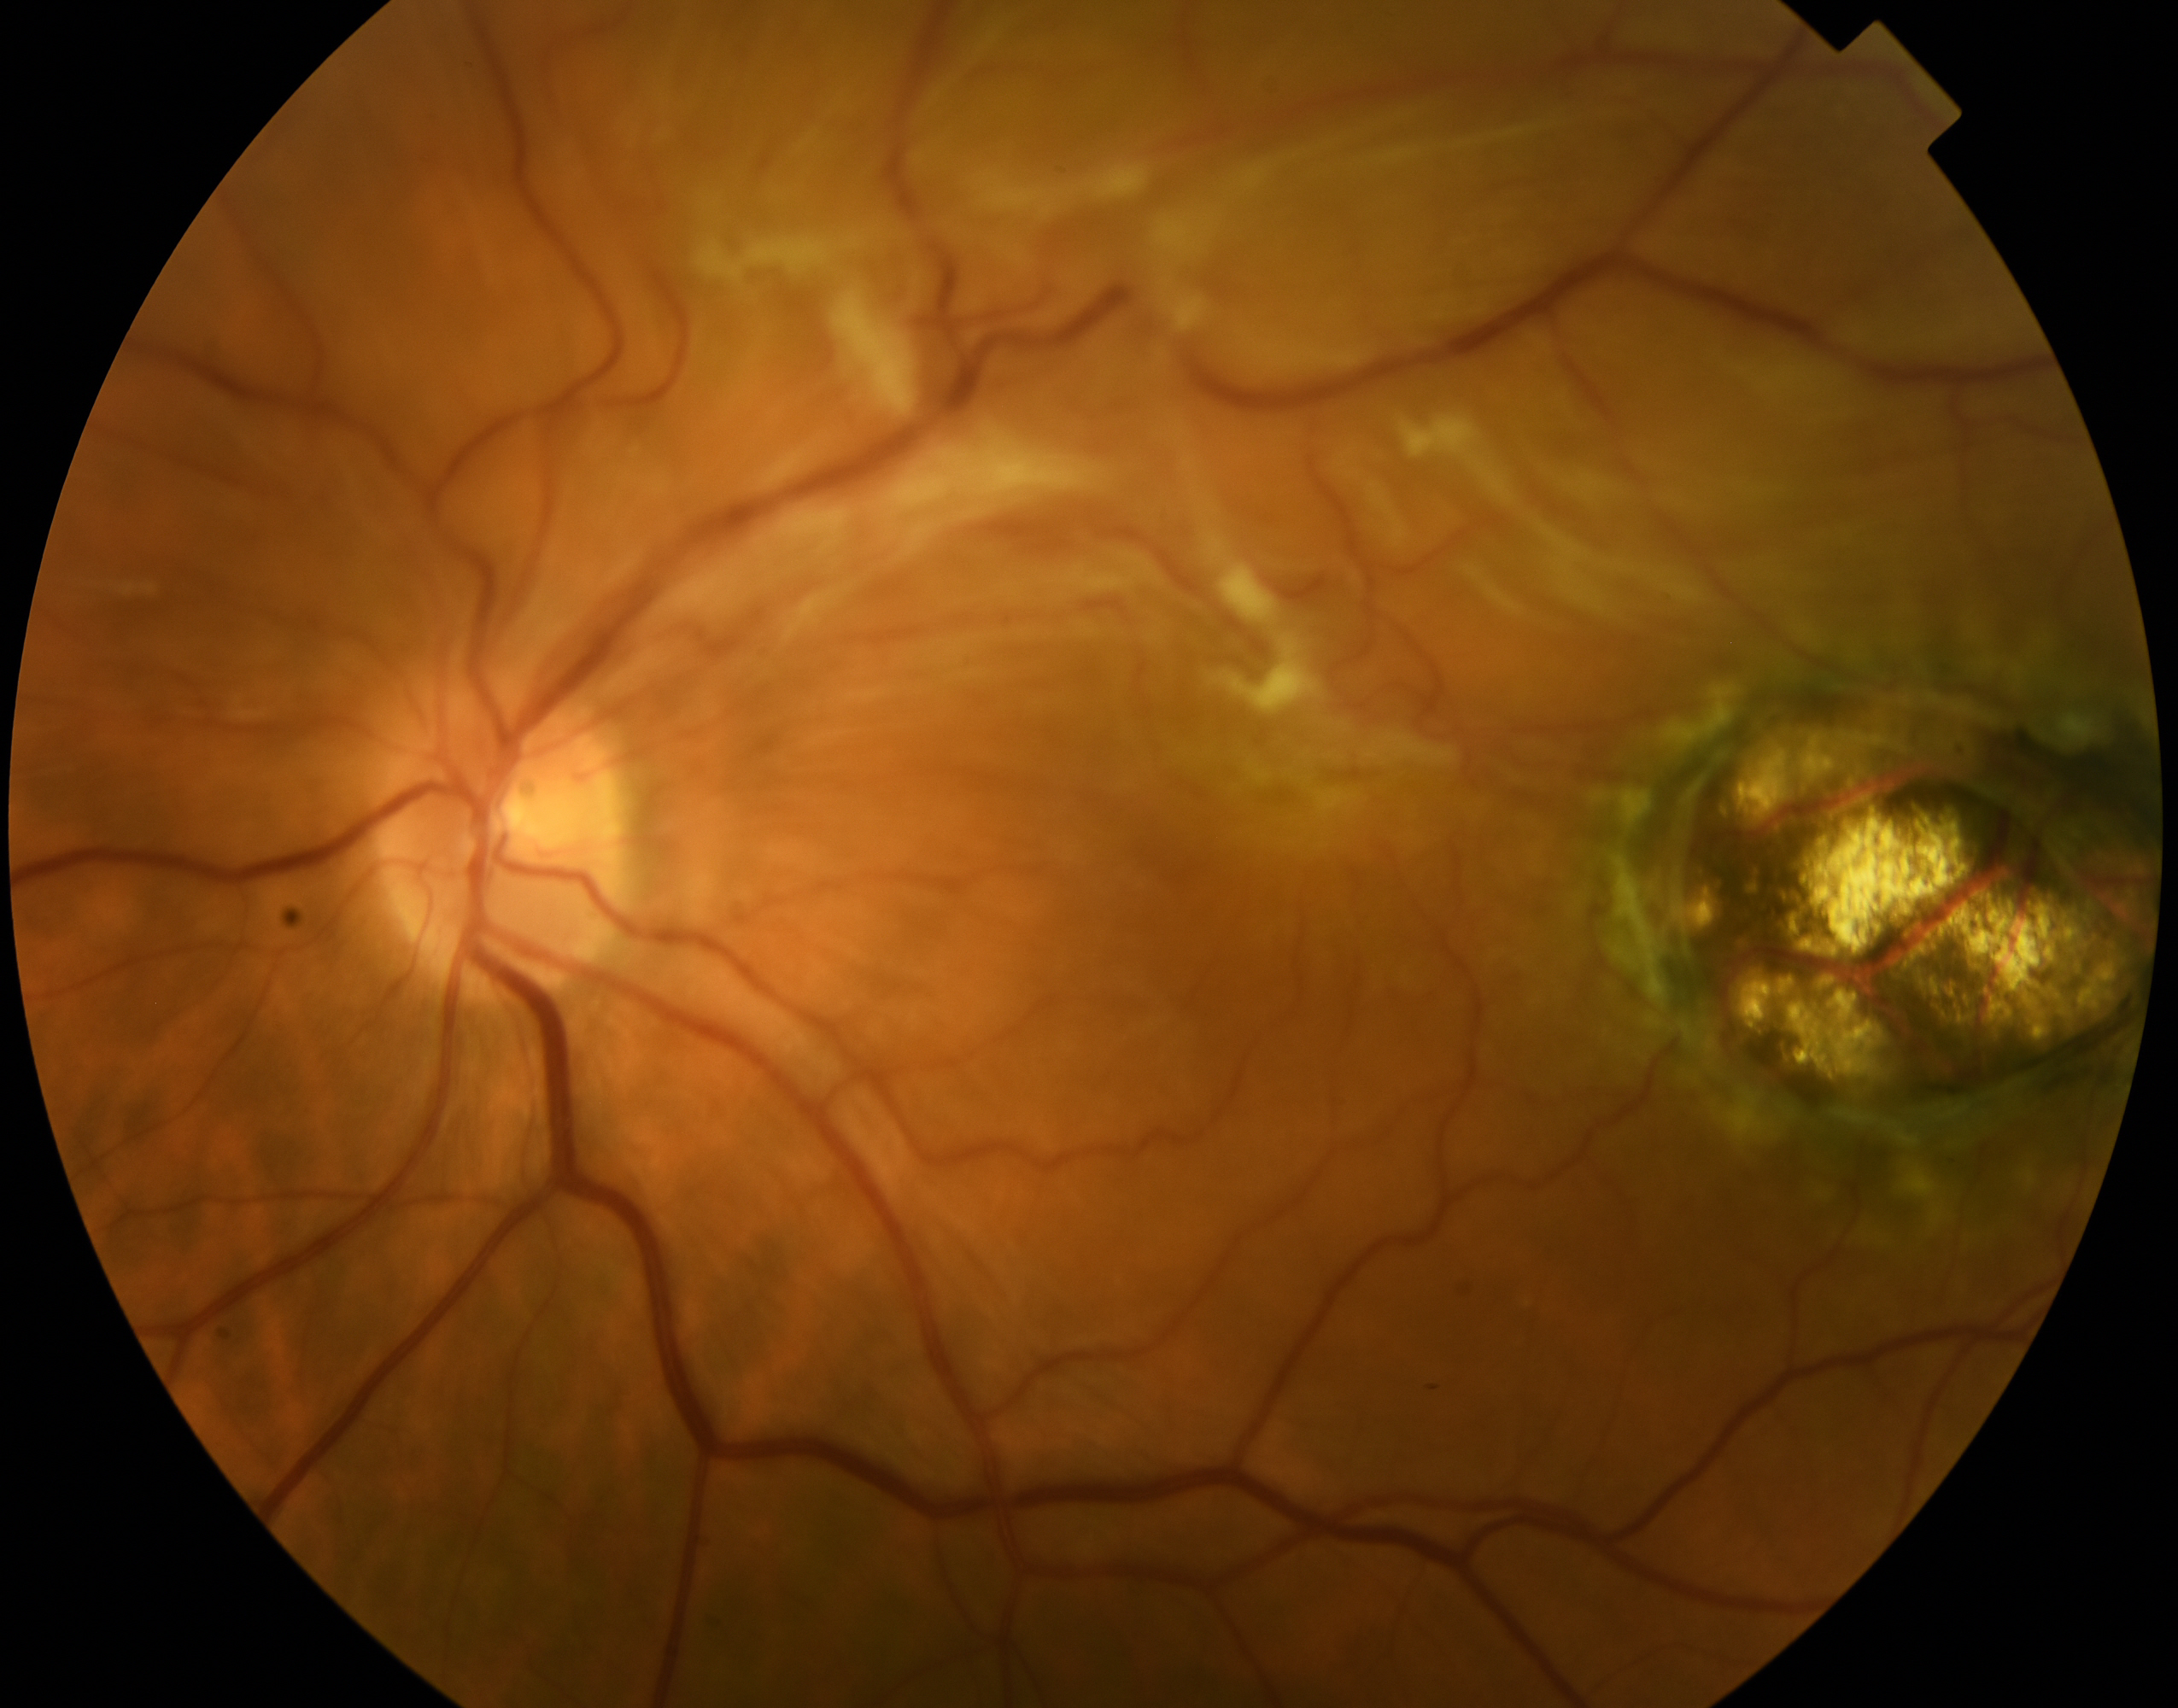

Retinopatia Diabetica

Degenerazione Maculare Senile